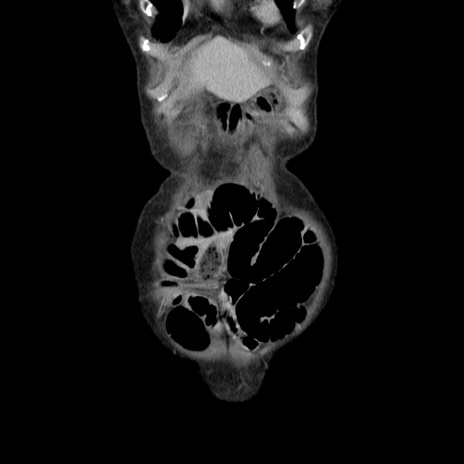

横断像

【症例】80歳代女性

【主訴】胸のつかえ感

【現病歴】約9時間前に食後から胸のつかえた感じあり、嘔吐あり、来院。

【既往歴】胃癌(全摘)、胆摘、虫垂炎

【身体所見】心窩部に圧痛あり、反跳痛なし。

【データ】WBC 5700、CRP 0.05